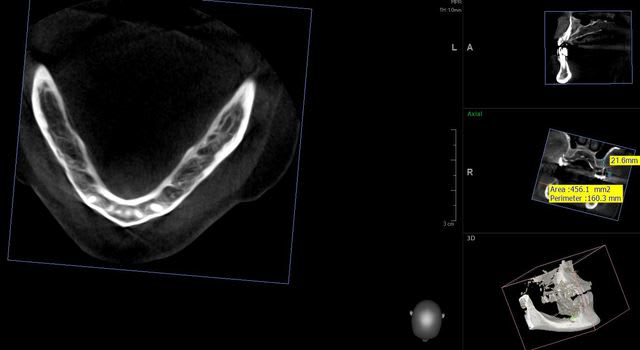

je ne me lasse pas de mon dernier joujoux...

quel précision!

implants posée le matin même..

comme on calibrait la morita, j'en ai profité pour faire un champs 10*8

je sens que je vais apprendre à poser des implants avec les contrôles post op.

en Russie le scanner est obligatoire tout les ans à la suite d'une pose d'implant. un peu excessif mais cela permet d'avoir du recule sur la façon dont pose ses implants.